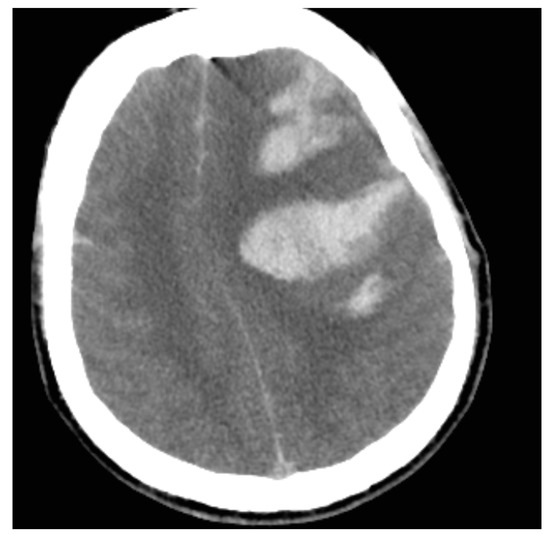

3.5. Imaging Studies